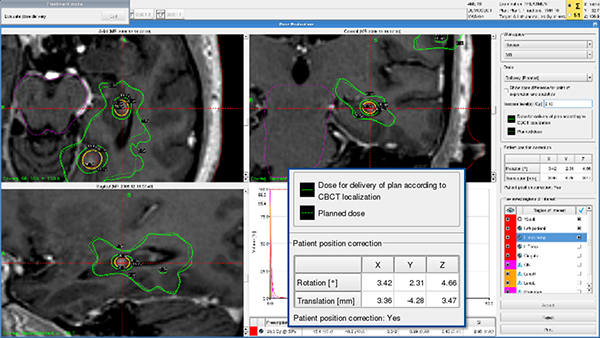

■ Online Adaptive DoseControl & Virtual 6D Couch

Iconでは6軸天板を装備していません。プレプランのMRI画像とステレオタクティックCBCT画像から得られた現在の患者体位画像を基準に,レジストレーションを行います。Virtual 6D Couchと呼ばれるソフトウェアによって,治療計画を現在の患者体位に合わせてAdaptiveに補正を行います。この機能によって,治療計画の質(Coverage, Selectivity, GI)を殆ど変えることなく補正することが可能です。

■ Online Adaptive DoseControl & Online Dose Evaluation

Virtual 6D Couchによって現在の体位に合った補正をした治療計画と,MRIで作成したプレプラン,そして補正後の治療計画の線量を瞬時に表示し,線量のEvaluationが可能です。ほとんどの場合は不要ですが,十分な補正結果でない場合には直ちにリプランも可能です。